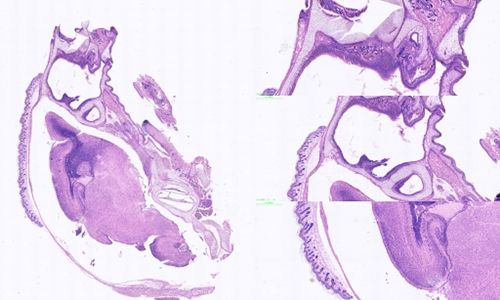

冰冻切片和石蜡切片是常见的组织学研究中的两种切片技术,它们在样本处理和切片制备过程中存在一些区别。

扫描切片

切片质量方面:冰冻切片相对于石蜡切片来说,切片质量可能稍差。由于冰冻切片的过程较快,切片的质量受到冷冻状态的影响,容易出现组织断裂、伪影和冰晶等问题。而石蜡切片在固定和浸泡处理后,组织样本得到更好地保护,切片质量相对较好。

切片的用途方面:冰冻切片主要用于快速初步观察和诊断,例如快速冰冻切片可以用于术中病理诊断。而石蜡切片则适用于各种组织学研究,包括光镜下观察、免疫组化染色和分子生物学研究等。